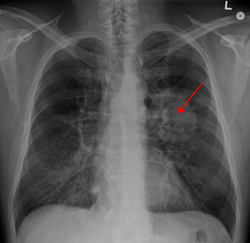

Döş qəfəsinin rentgenindən ağciyərdəki şiş görünür (oxla göstərilib)

Ağciyər xərçənginin simptomları xəstəliyin harada başlandığından, necə yayıldığından və bədənin xəstəliyə reaksiyalarından asılı olaraq dəyişə bilir. Ən çox müşahidə edilən simptomları nəfəs daralması, öskürək (qanlı öskürək - hemoptizis də daxil) və çəki itkisidir. Bu simptomlar sadəcə ağciyər xərçənginə xas olmadığından xərçəng diaqnozu qoyulması gecikə bilər. Ağciyər xərçəngi döş qəfəsi rentgeni və kompüter tomoqrafiyası ilə görülə bilər. Dəqiq diaqnoz biopsiya ilə qoyulur. Biopsiya, adətən, bronxoskopiya və ya kompüter tomoqrafiyası köməkliyi ilə edilir. Müalicə və proqnozu müəyyən edən amillər xərçəngin histoloji tipi, xərçəngin mərhələsi və xəstənin ümumi vəziyyətidir. Ağciyər xərçənginin bir çox histoloji alt tipləri olmasına baxmayaraq klinikada, adətən, kiçik hüceyrəli və kiçik olmayan hüceyrəli ağciyər xərçəngi olmaq üzrə iki başlıqda araşdırılır, çünki müalicədə gediləcək yol bu qruplaşmadan asılıdır. Kiçik hüceyrəli ağciyər xərçəngi müalicəsində kimyaterapiya və radioterapiyaya üstünlük verilir. Kiçik olmayan hüceyrəli xərçənglərdə ilk seçim cərrahiyyədir.